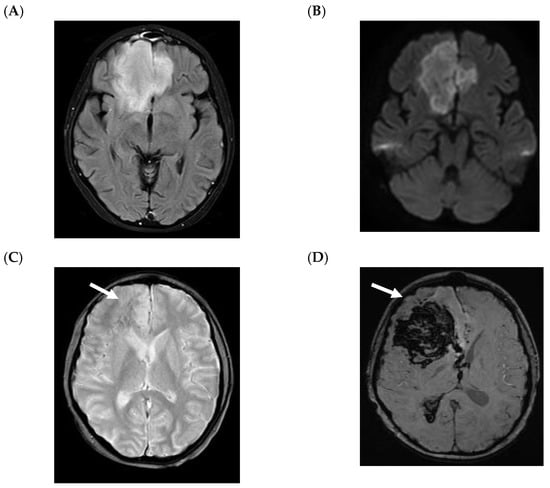

5.2. CNS Manifestations

- Nickerson, J.P.; Richner, B.; Santy, K.; Lequin, M.H.; Poretti, A.; Filippi, C.G.; Huisman, T.A. Neuroimaging of pediatric intracranial infection--part 2: TORCH, viral, fungal, and parasitic infections. J. Neuroimaging 2012, 22, e52–e63. [Google Scholar] [CrossRef] [PubMed]

- Gavito-Higuera, J.; Mullins, C.B.; Ramos-Duran, L.; Olivas Chacon, C.I.; Hakim, N.; Palacios, E. Fungal Infections of the Central Nervous System: A Pictorial Review. J. Clin. Imaging Sci. 2016, 6, 24. [Google Scholar] [CrossRef]

- Antulov, R.; Dolic, K.; Fruehwald-Pallamar, J.; Miletic, D.; Thurnher, M.M. Differentiation of pyogenic and fungal brain abscesses with susceptibility-weighted MR sequences. Neuroradiology 2014, 56, 937–945. [Google Scholar] [CrossRef]

- Mathur, M.; Johnson, C.E.; Sze, G. Fungal infections of the central nervous system. Neuroimaging Clin. N. Am. 2012, 22, 609–632. [Google Scholar] [CrossRef]

- Britt, R.H.; Enzmann, D.R.; Placone, R.C., Jr.; Obana, W.G.; Yeager, A.S. Experimental anaerobic brain abscess. Computerized tomographic and neuropathological correlations. J. Neurosurg. 1984, 60, 1148–1159. [Google Scholar] [CrossRef] [PubMed]